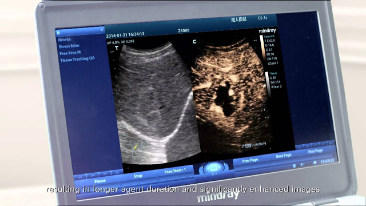

Tecnologia trasduttore 3T con cristallo singolo

Fornendo immagini pi├╣ nitide, tutte le sonde compatibili con M9 sono dotate della tecnologia Mindray tecnologia trasduttore 3T, unica nel suo genere. Migliorato con l'aggiunta della tecnologia monocristallo, M9 offre una migliore penetrazione e un flusso dinamico del colore, in particolare durante la scansione di pazienti difficili.

La funzionalit├Ā TT QA (Tissue Tracking Quantitative Analysis) di M9 consente una soluzione semplice, veloce e non invasiva per la valutazione di anomalie parietali del ventricolo sinistro. Supportato dalla tecnologia Mindray brevettata 3T con monocristallo, M9 migliora significativamente la precisione di tracciamento e l'efficacia, controllando la deviazione dell'immagine causata dal movimento della sonda e dalla respirazione. Grazie al vantaggio unico aggiunto dellŌĆÖanalisi in loco, il TT QA su M9 pu├▓ essere eseguito al letto del paziente, risparmiando tempo e rendendo molto pi├╣ semplici le diagnosi complesse.